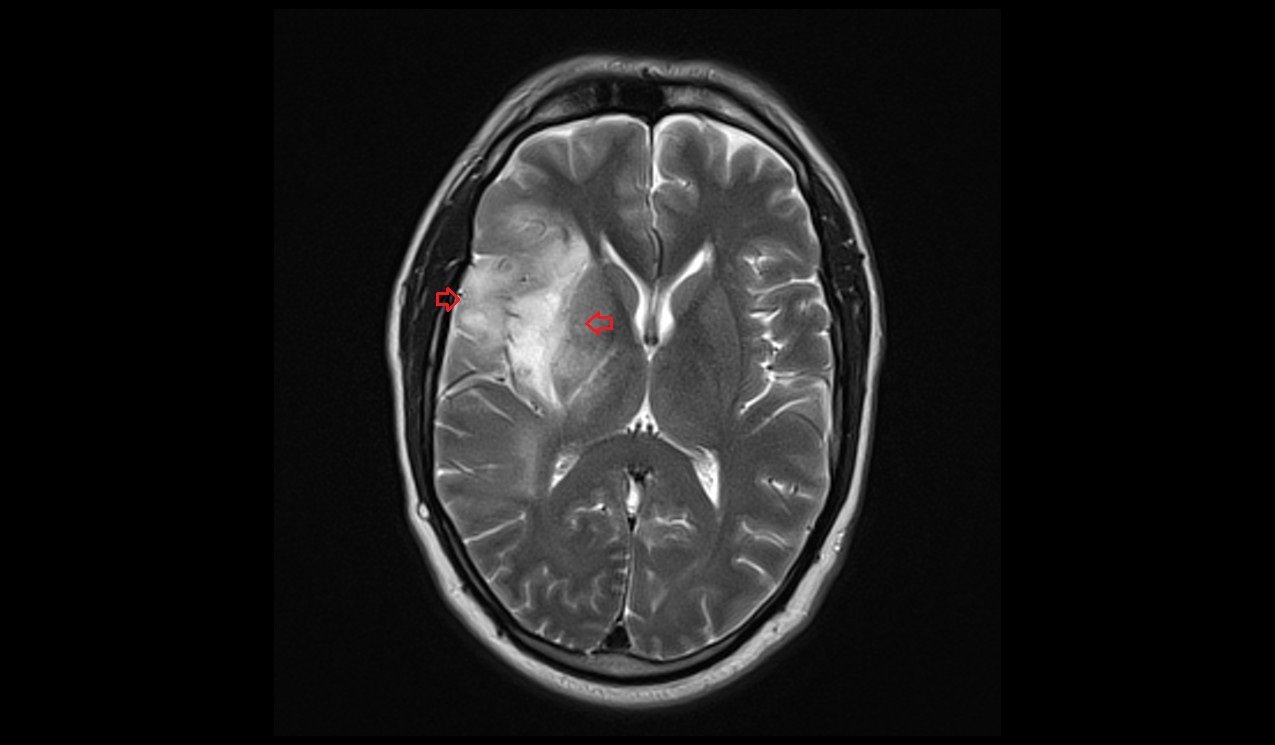

Oligodendroglioma arise mainly in the frontal lobe and in 50–80% of cases, the first symptom is the onset of seizure activity, without having any symptoms beforehand. Headaches combined with increased intracranial pressure are also a common symptom of oligodendroglioma. Depending on the location of the tumor, many different neurological and neuropsychological deficits can be induced, including, but not limited to, visual loss, motor weakness, cognitive decline, and anxiety. A computed tomography (CT) or magnetic resonance imaging (MRI) scan is necessary to characterize tumor size, location, and hetero- or homogeneity. Final diagnosis relies on biopsy and histopathologic examination of the tumor mass.

Oligodendrogliomas cannot currently be differentiated from other brain lesions solely by their clinical or radiographic appearance. As such, a brain biopsy is the only method of definitive diagnosis. Oligodendrogliomas recapitulate the appearance of the normal resident oligodendroglia of the brain. (Their name derives from the Greek roots 'oligo' meaning "few" and 'dendro' meaning "trees".) They are generally composed of cells with small to slightly enlarged round nuclei with dark, compact nuclei and a small amount of eosinophilic cytoplasm. They are often referred to as "fried egg" cells due to their histologic appearance (though, the perinuclear halo on permanent sections is an artifact of tissue drying; fresh tissue lacks this characteristic "fried egg" appearance). They appear as a monotonous population of mildly enlarged round cells infiltrating normal brain parenchyma and producing vague nodules. Although the tumor may appear to be vaguely circumscribed, it is by definition a diffusely infiltrating tumor.